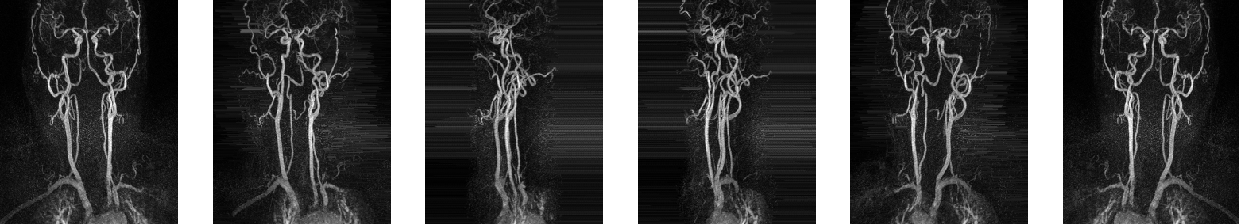

2.2 Segmentation of MIP images

We first solve a 2D version of our problem. This can be done by applying maximum intensity projections to the 3D data and the corresponding 3D ground truths. Using a rotation angle of around the vertical axis we obtain 10 MIP images out of each patient, which results in a data set to 1190 pairs of 2D images and corresponding 2D segmentation masks. Data corresponding for one patient are shown in Figure 2.1.